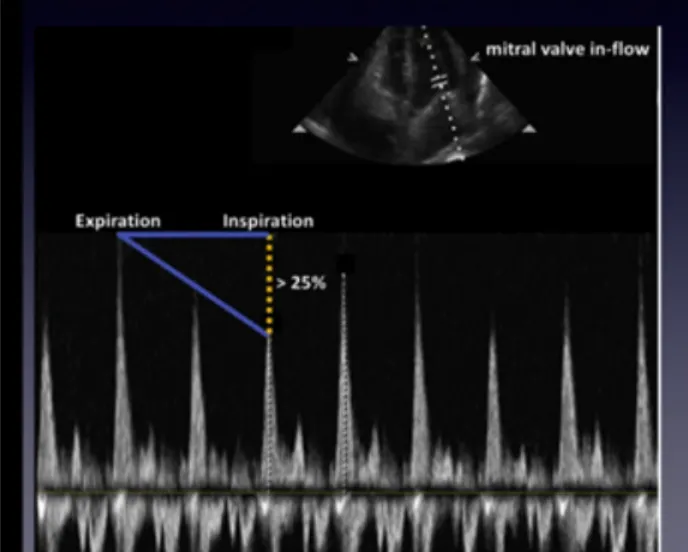

A5. 호흡에 따라 MV inflow velocity의 차이 발생

•

pulsus paradoxus의 대용으로 생각하면 됨.

A4C view에서 PW Doppler 적용하고 MV opening 에 커서위치

: 정상적으로라면 Exp& insp. 차이는 25%가 넘으면 안됨.